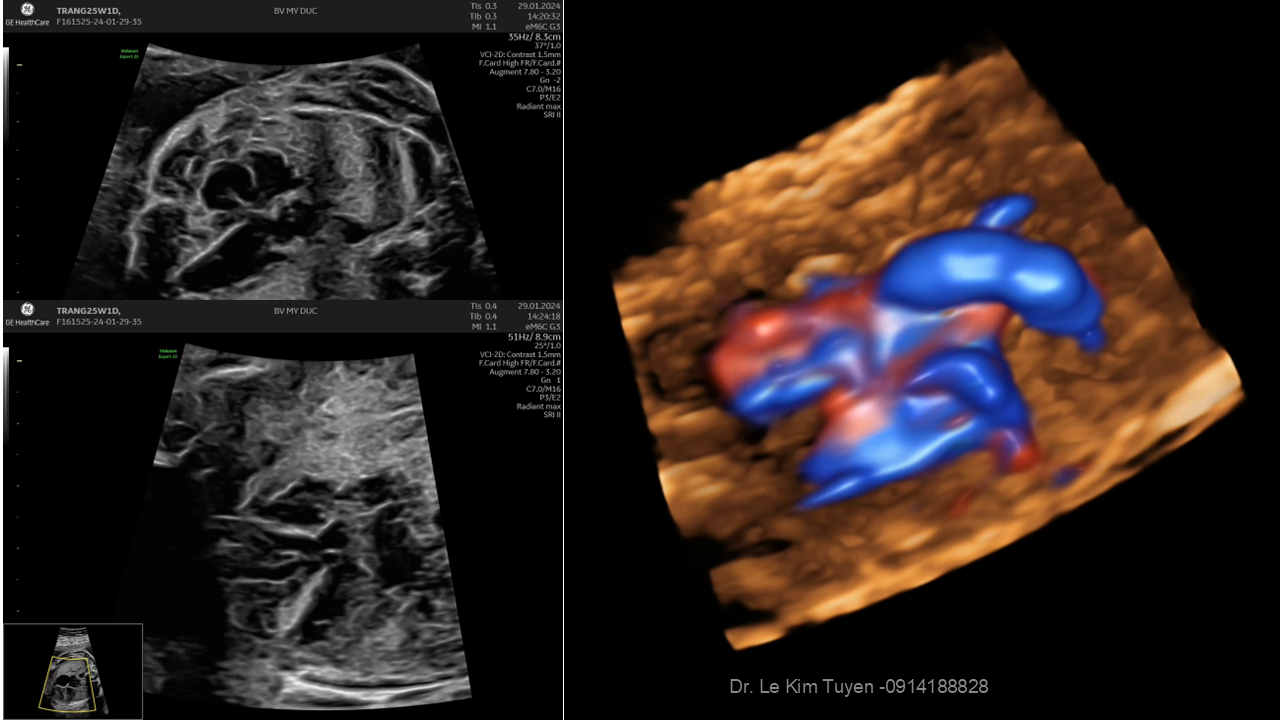

Áp dụng công nghệ Graphicflow trong phát hiện bệnh tim bẩm sinh cần cấp cứu sơ sinh

TS. BS. Lê Kim Tuyến

Bệnh viện Tim Tâm Đức